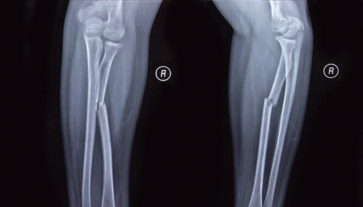

- Radiografie